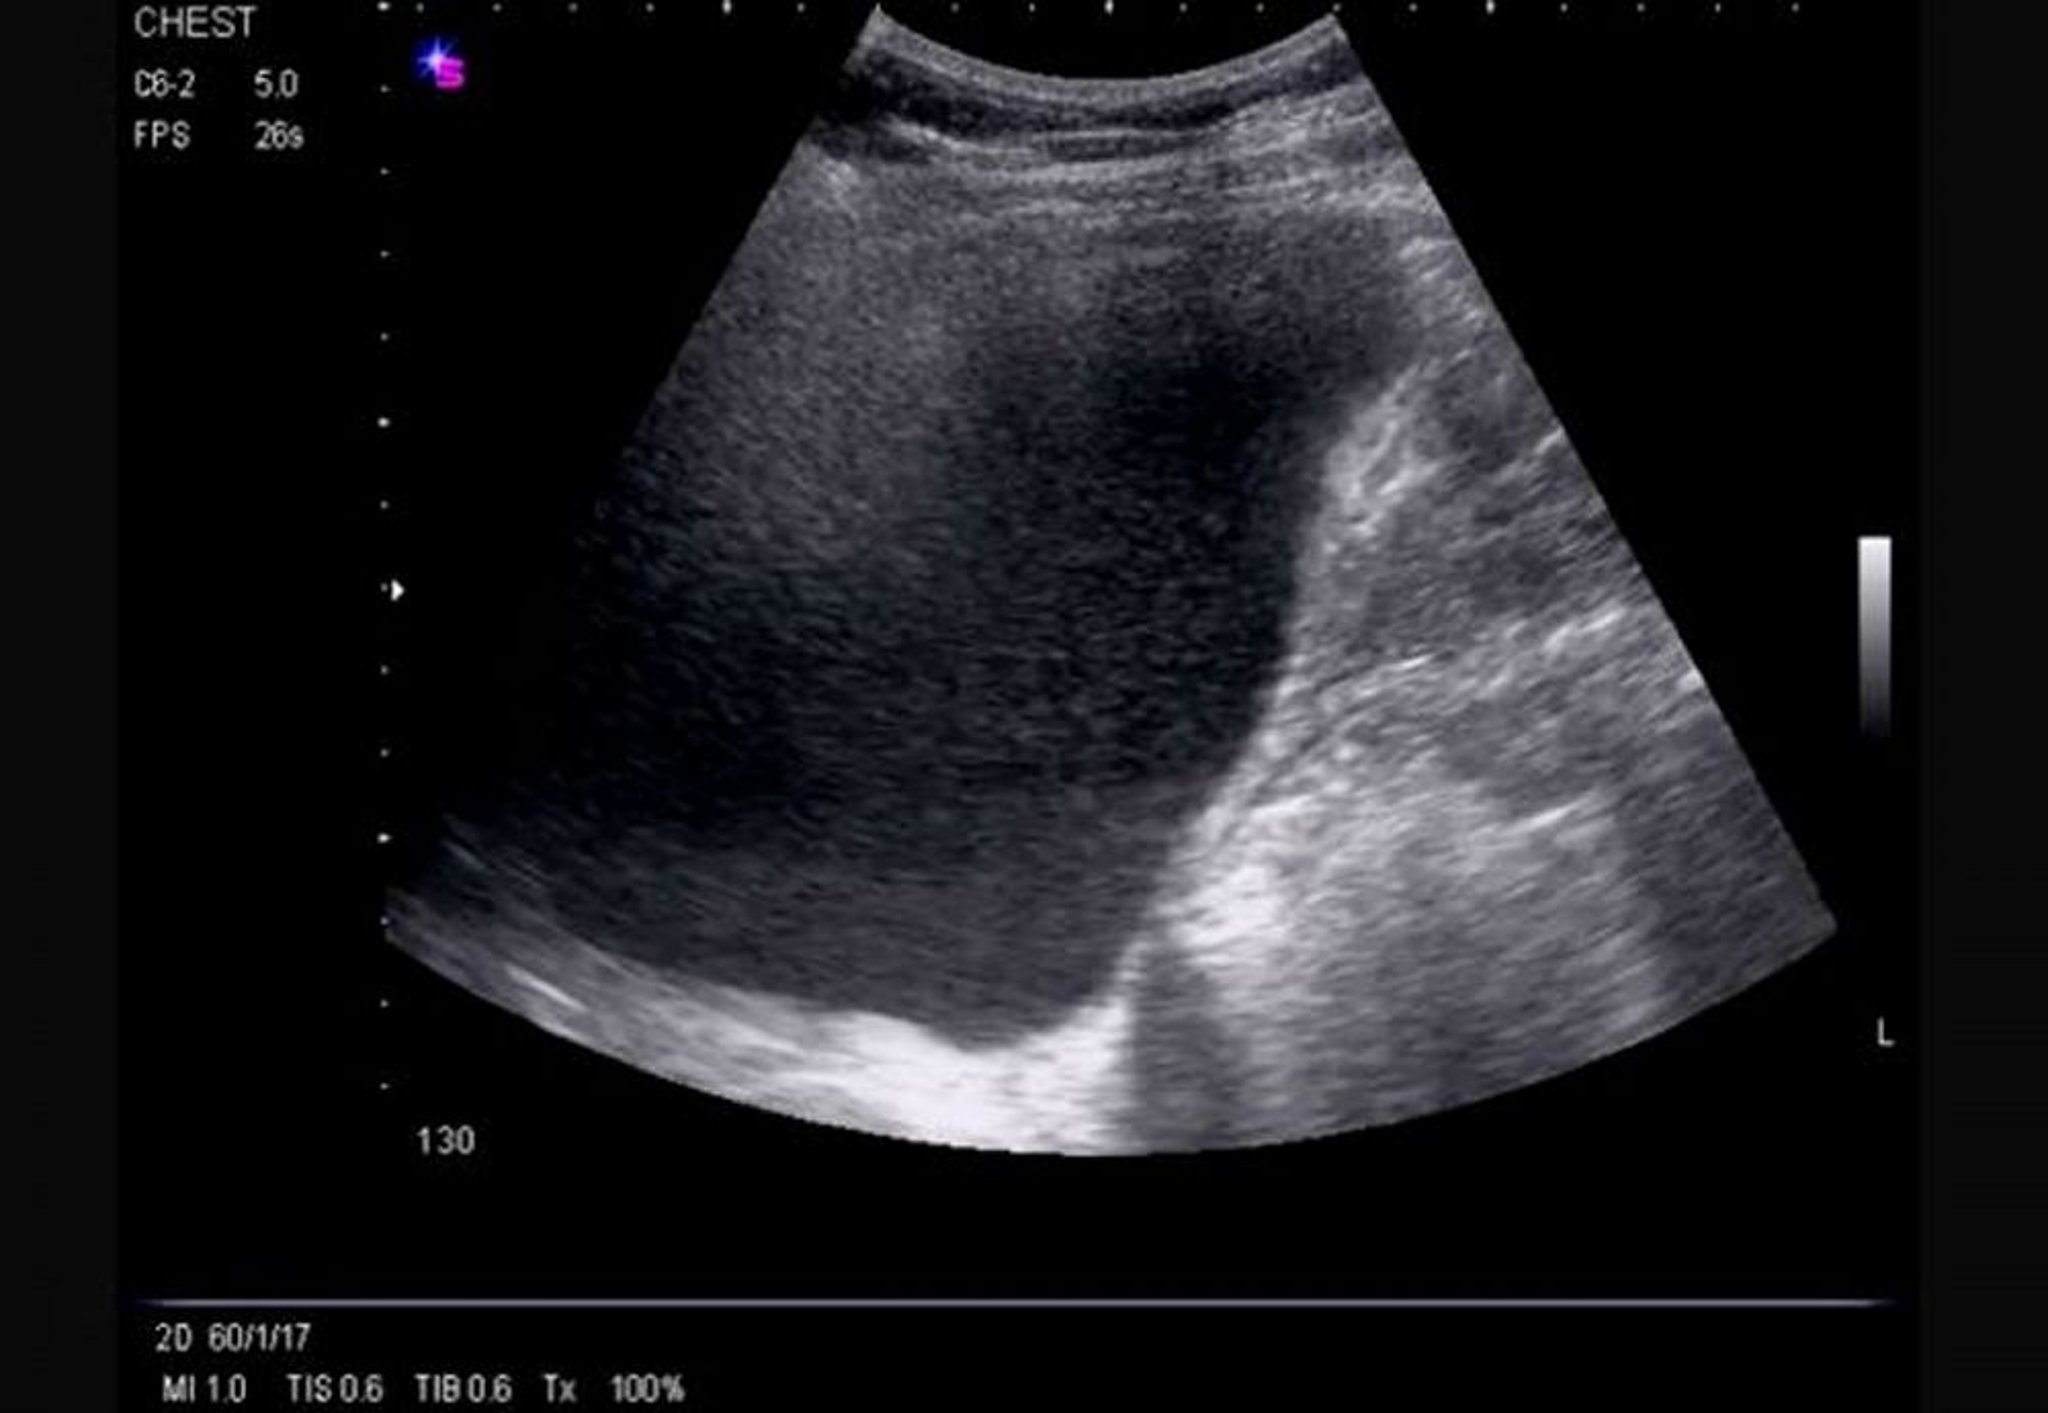

Lateral Thoracic Ultrasound (Right)

This ultrasound shows a massive, right-sided, free-flowing effusion causing inversion of the hemidiaphragm and demonstrating echogenicity.

Image courtesy of Najib M. Rahman, BMBCh MA (oxon) DPhil.